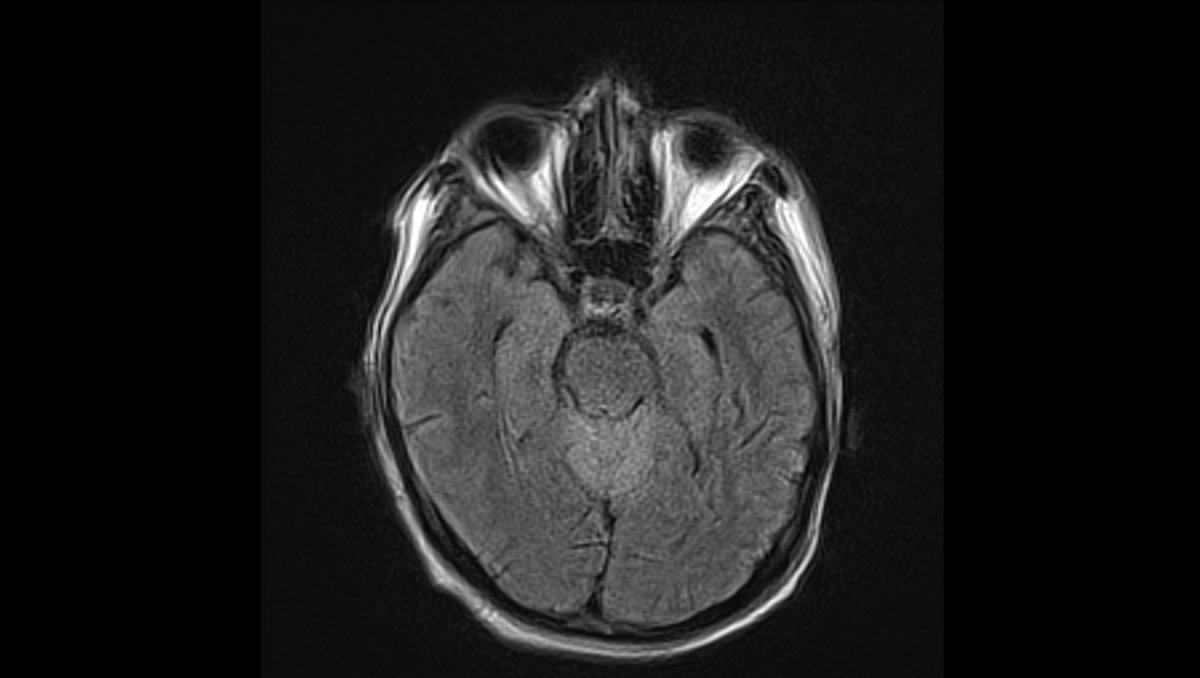

症例1:28歳男性

- 体動困難、呂律不良

- 4か月ほど前から歩行時の息切れあり、1か月前から下肢の疼痛が出現、1週間前からはベッド上で生活していた。

- 3日前から呂律が緩慢となり、増悪したため、父親が救急要請。